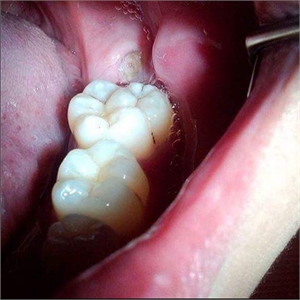

Teeth gemination in molars

Gemination can be described as teeth ‘twinning’. In dental context, gemination refers to a developmental irregularity in which a single tooth germ divides resulting in a bifid crown on a single root, that is, two teeth develop together from a single tooth bud. The two parts of the double tooth will be exact images of each other. It is seen as a cleft crown on x-rays where the radiopaque enamel outlines the invagination.

6. The grooves marking the two crown portions may provide a niche to harbour plaque and debris which make the tooth susceptible to dental caries

7. Periodontal health is also at risk due to plaque accumulation